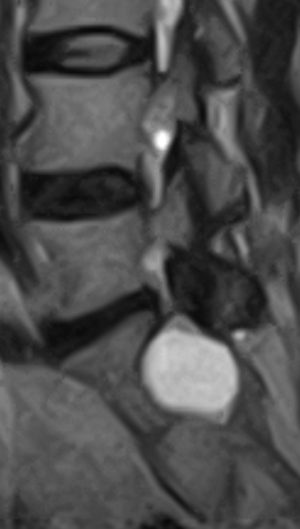

(Справа) Т1-ВИ, сагиттальная проекция: в спинномозговом канале крестца определяется небольшая экстрадуральная киста, интенсивность сигнала которой соответствует жидкости. Такая локализация типична для скрытого крестцового менингоцеле, которое в настоящее время носит название экстрадуральной арахноидальной кисты. В полости кисты не определяется ни солидного, ни жирового компонентов. (Слева) На сагиттальном Т2-ВИ в каудальной части спинномозгового канала визуализируется небольшая экстрадуральная арахноидальная киста крестца. Конус спинного мозга оканчивается на нормальном уровне. Обратите внимание на то, что интенсивность сигнала от кисты несколько выше, чем от СМЖ в дуральном мешке, что отражает повышенное содержание в полости кисты белка.

• Дивертикул крестцового субарахноидального пространства, превращающийся в кисту с последующим вторичным ремоделированием крестцового канала

• Экстрадуральная арахноидальная киста, отсутствует пролабирование мозговых оболочек (не истинное менингоцеле)

• Киста соединяется с дуральным мешком тонким тяжом

• Нервные образования в полости кисты отсутствуют